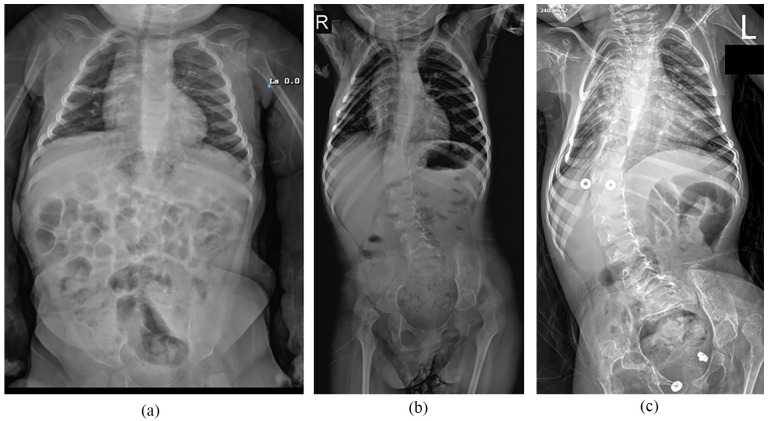

Methods: In a retrospective study, 29 spinal muscular atrophy type 1 patients born between 2017 and 2021, confirmed by genetic testing, treated with intrathecal nusinersen, and had registered to the national electronic health database were included. Demographics, age at the first nusinersen dose, total administrations, and Children's of Philadelphia Infant Test of Neuromuscular Disorders scores were collected. Radiological assessments included parasol rib deformity, scoliosis, pelvic obliquity, and hip subluxation.

Results: Mean age was 3.7 ± 1.1 (range, 2-6), and average number of intrathecal nusinersen administration was 8.9 ± 2.9 (range, 4-19). There was a significant correlation between Children's of Philadelphia Infant Test of Neuromuscular Disorders score and the number of nusinersen administration (r = 0.539, p = 0.05). The correlation between Children's of Philadelphia Infant Test of Neuromuscular Disorders score and patient age (r = 0.361) or the time of first nusinersen dose (r = 0.39) was not significant (p = 0.076 and p = 0.054, respectively). While 93.1% had scoliosis, 69% had pelvic obliquity, and 60.7% had hip subluxation, these conditions showed no significant association with patient age, total nusinersen administrations, age at the first dose, or Children's of Philadelphia Infant Test of Neuromuscular Disorders scores.

Abstract Image